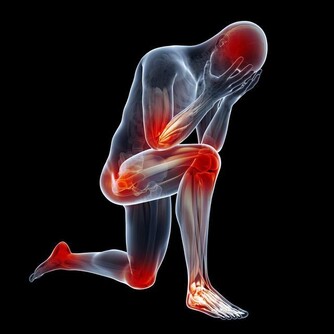

當動脈血管堵塞75%以上,血流量過少時,胸悶、氣短、頭暈、頭痛等不適就會出現,更嚴重還會誘發腦卒中、心肌梗死等疾病。

早點「養」血管,勝於老來「治」。因此清理血管,永遠都不嫌遲,有什麼有效的方法能及時的清理我們血管中的廢物呢?